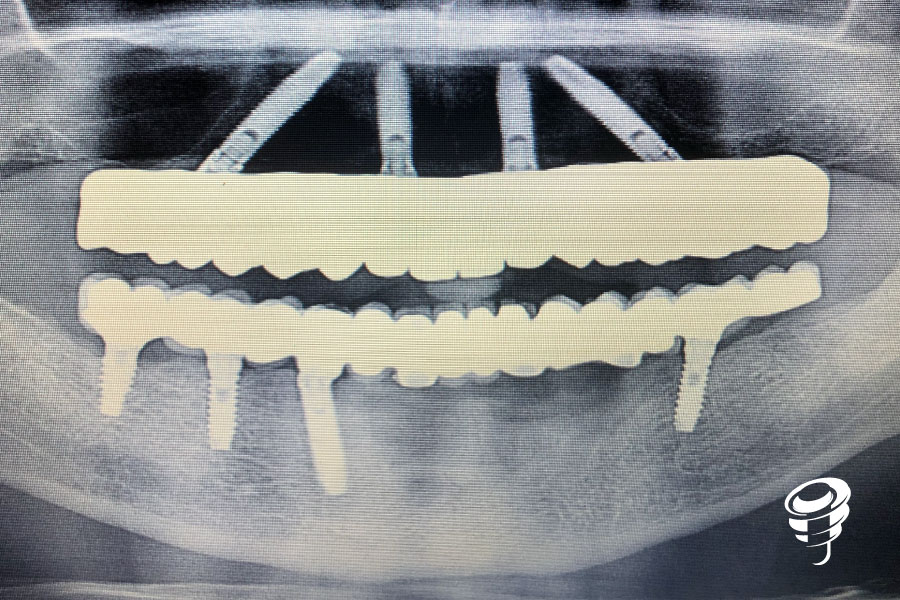

Figura 1. Radiografía inicial – Ortopantomografía

Tras realizar un diagnóstico clínico y radiográfico, con la ortopantomografia apreciamos el gran defecto óseo vertical tras la explantación.

Rehabilitación definitiva fija sobre todos los implantes donde podemos apreciar el buen estado del nivel de hueso.